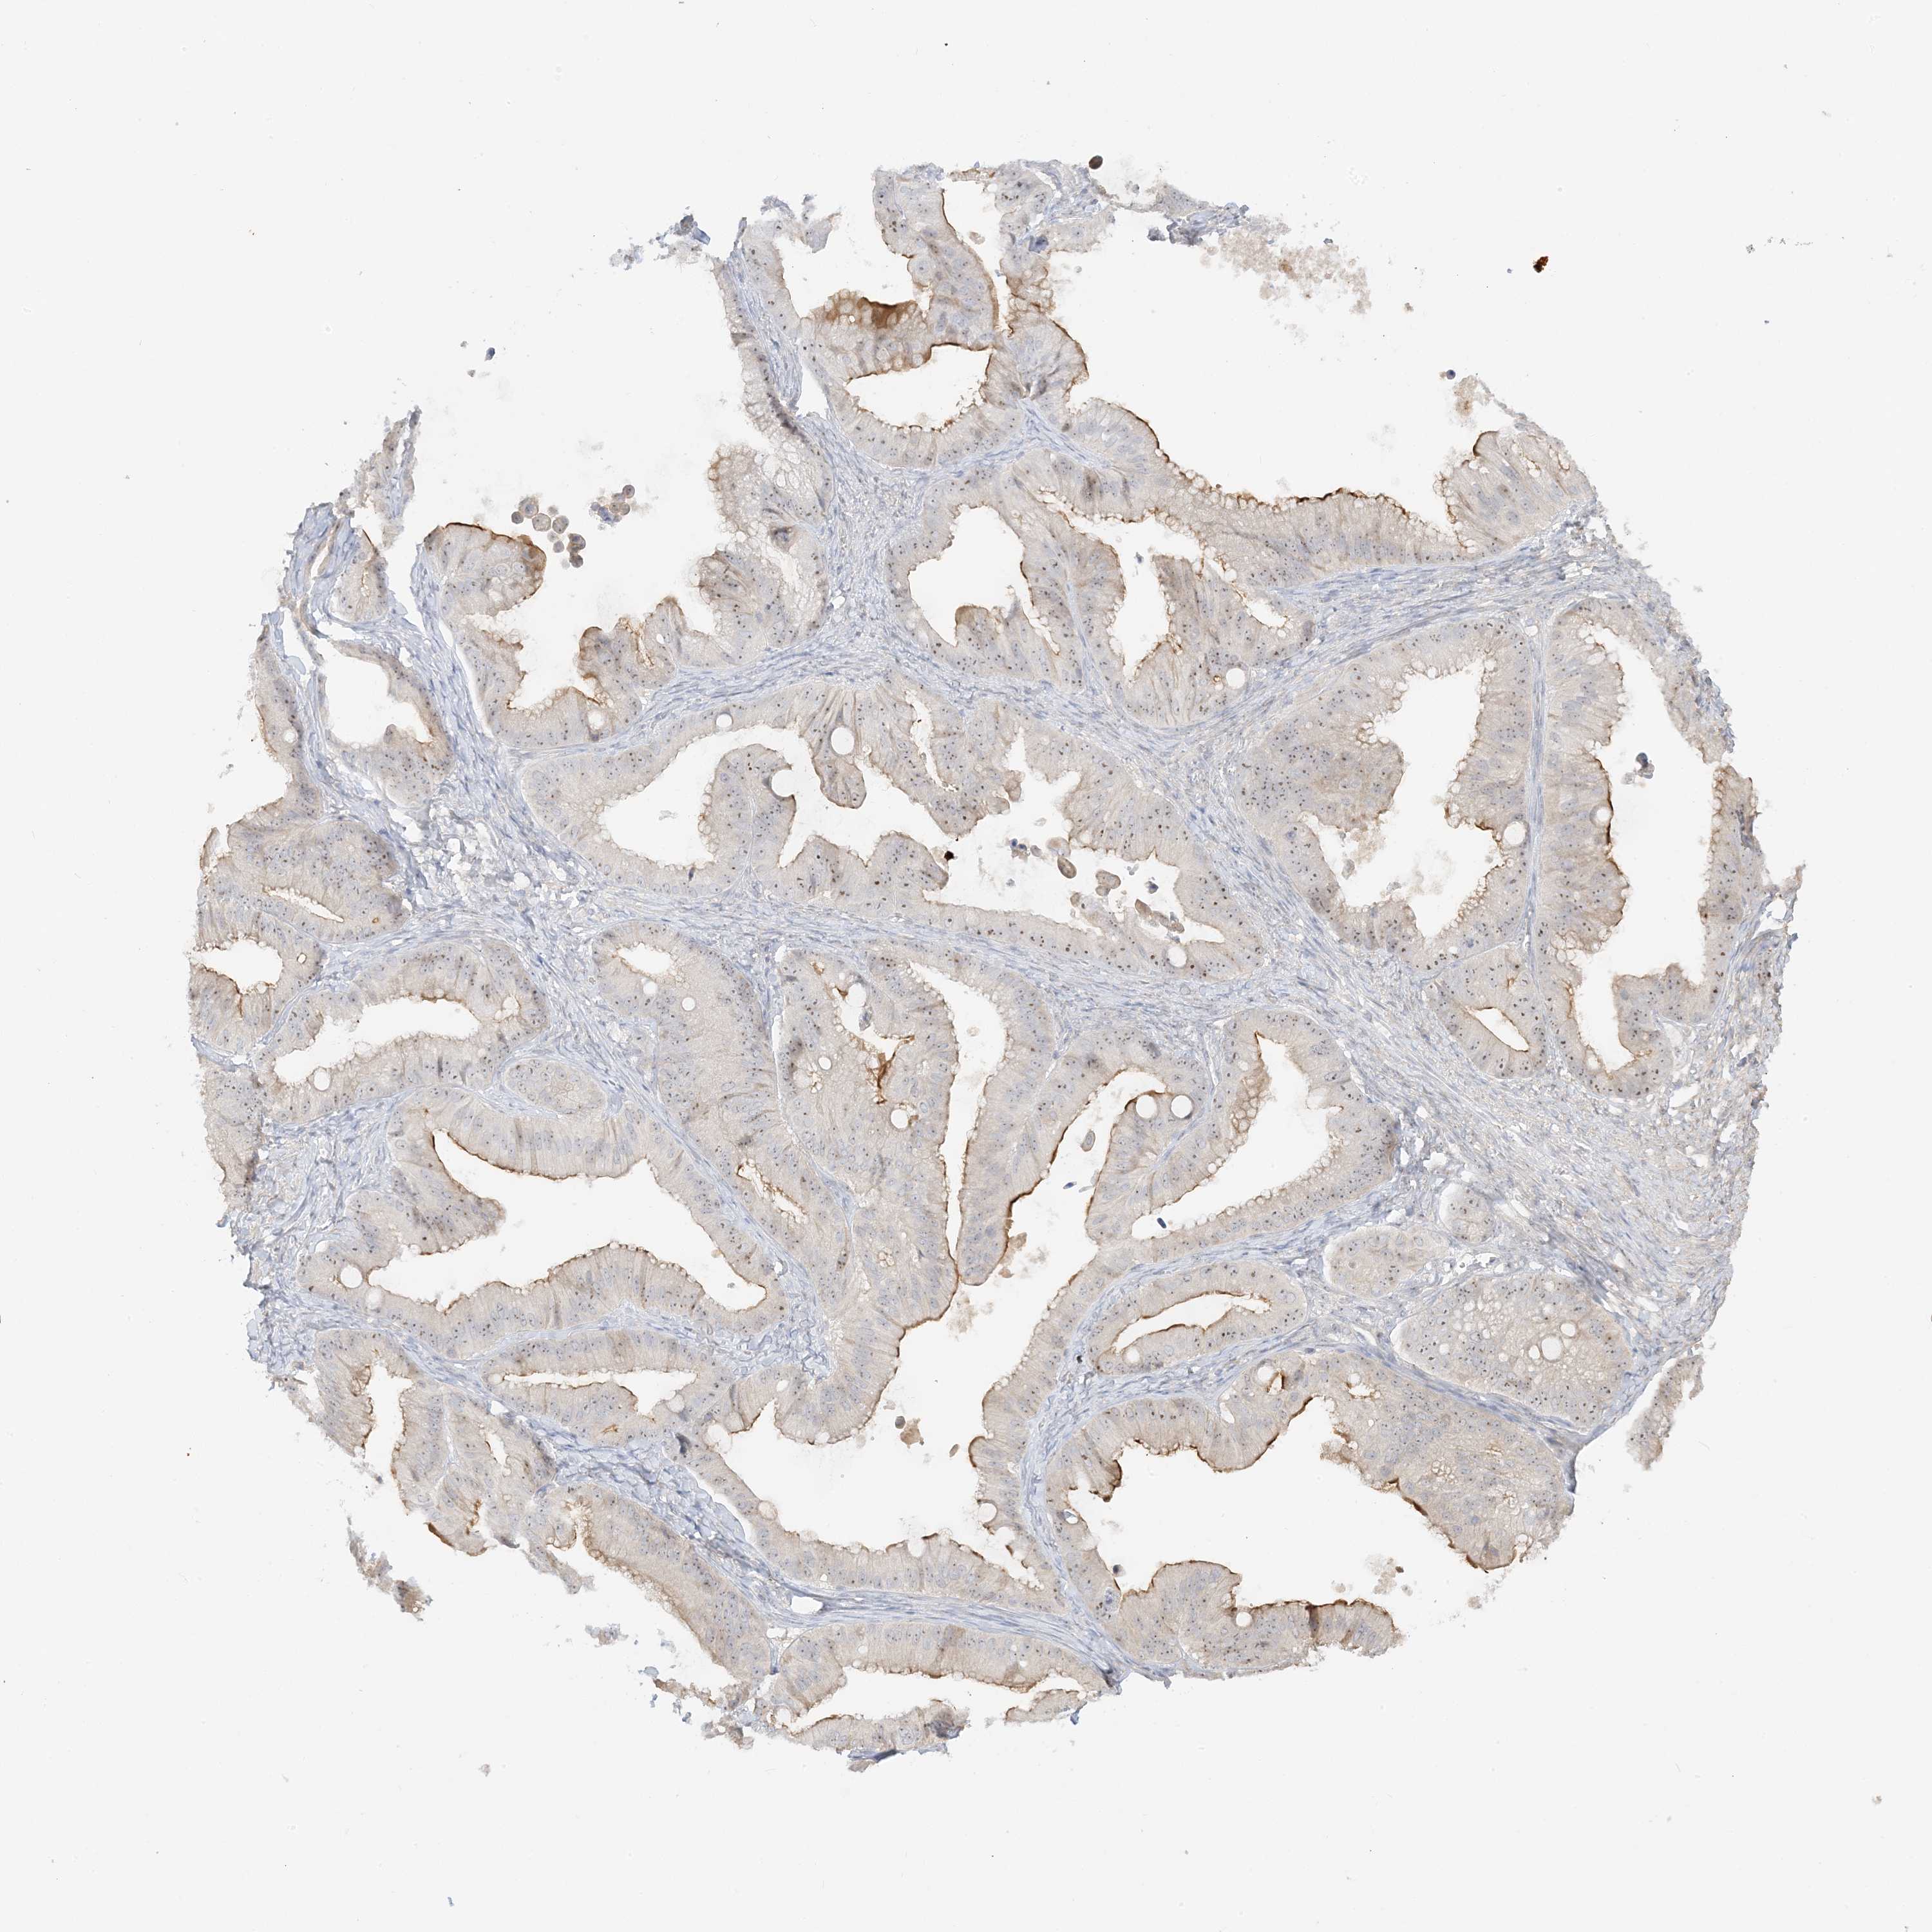

OVARIAN CANCER - Protein expressioni

A mouse-over function shows sample information and annotation data. Click on an image to view it in a full screen mode. Samples can be filtered based on level of antibody staining by selecting one or several of the following categories: high, medium, low and not detected. The assay and annotation is described here.

Note that samples used for immunohistochemistry by the Human Protein Atlas do not correspond to samples in the TCGA dataset.

Antibody stainingi

Antibody staining in the annotated cell types in the current human tissue is reported as not detected, low, medium, or high, based on conventional immunohistochemistry profiling in selected tissues. This score is based on the combination of the staining intensity and fraction of stained cells.

Each image is clickable and will lead to virtual microscopy that enables deeper exploration of all samples and also displays staining intensity scores, fraction scores and subcellular localization as well as patient and tissue information for each sample.

Antibody HPA035048

Antibody HPA035049

Cystadenocarcinoma, mucinous, NOS